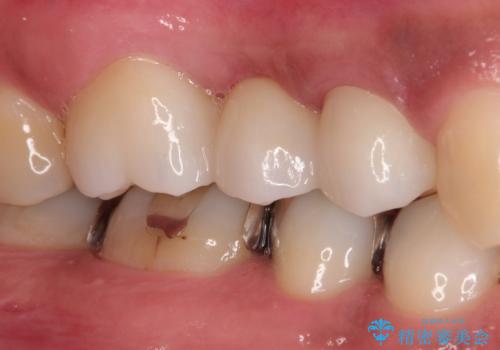

以前は保険治療で作られた金属のブリッジを装着されていましたが、オールセラミックブリッジを装着することにより、審美的にも改善されました。